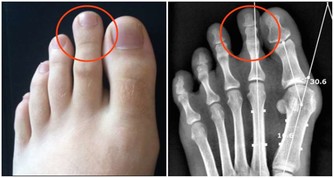

應及時發現乳房、睾丸、腹股溝、頸部、腹部、腋窩或其他部位的乳房異常,以探討癌症的危險性。值得注意的一點是:胸部小、足跟小不會與乳腺癌有關。

對於男性來說,如果乳房皮膚出現皺紋,收縮或不對稱乳頭,乳頭大小和形狀改變,乳房腫脹,腫塊出現,是炎症的表現,乳頭,乳腺癌的症狀。